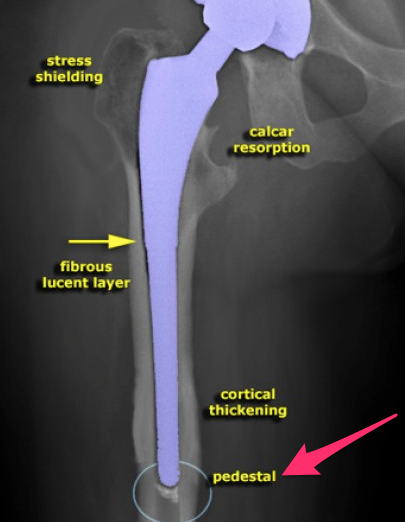

What is stress shielding?

Where is stress shielding most common?

What factors increase stress shielding?

What factors are important in stress shielding in proximal bone?

How is the extent of stress shielding evaluated?

What are the clinical implications of stress shielding of proximal femur?

What are the signs of uncemented implant failure?